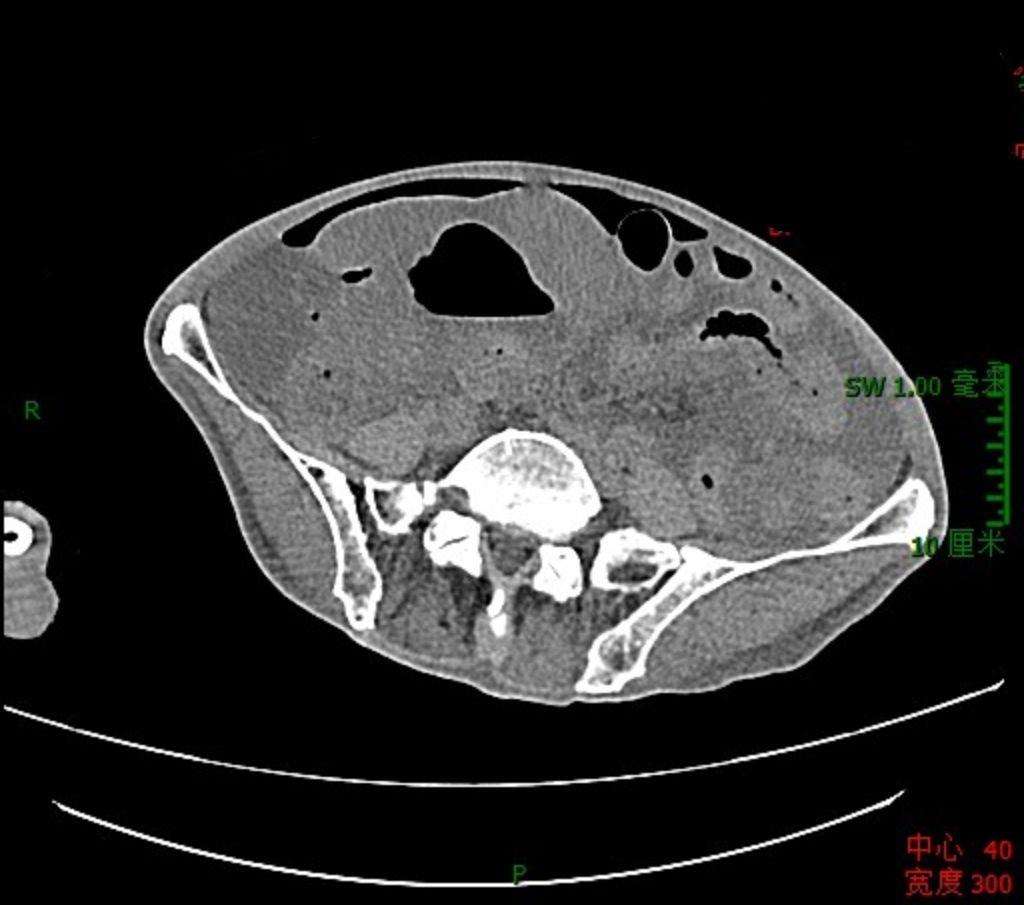

肠道淋巴瘤,最怕穿孔与梗阻,这是穿孔!